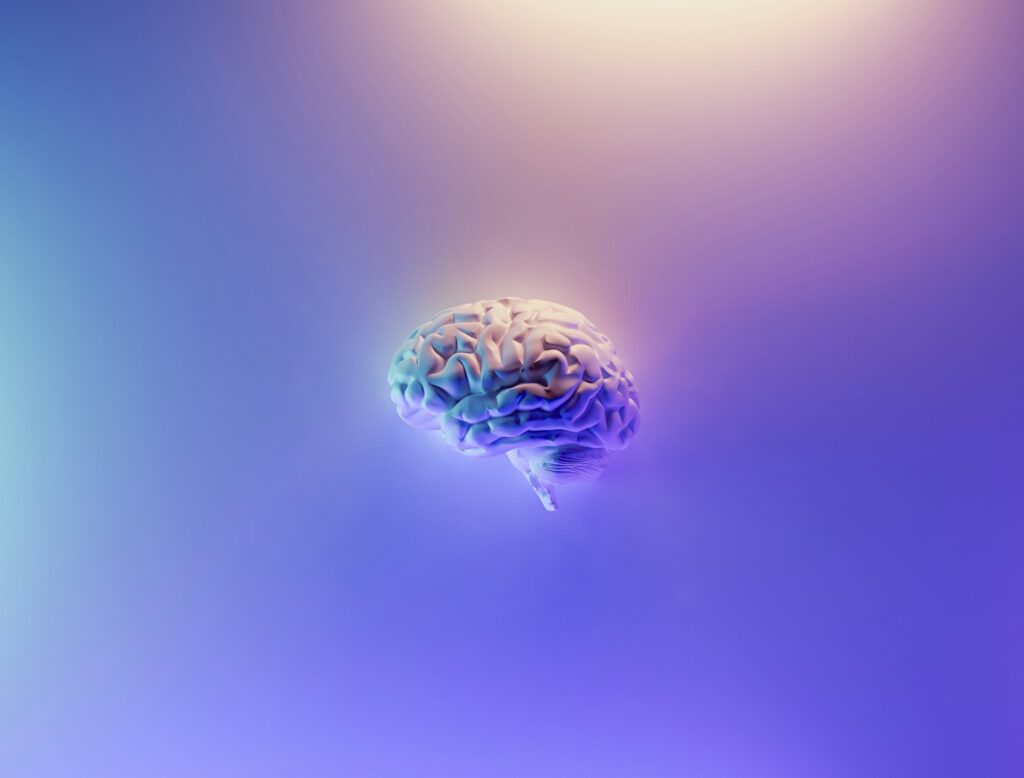

5. **Cognitive Difficulties: Navigating the ‘Brain Fog’ Phenomenon**Beyond physical symptoms, autoimmune disorders can profoundly affect cognitive function, leading to a phenomenon commonly referred to as “brain fog.” This is far more than simple forgetfulness; it encompasses a constellation of cognitive difficulties that significantly impact daily mental functioning. It involves pervasive problems with memory, concentration, and overall mental clarity, making it difficult to perform tasks that once seemed effortless.

Brain fog is a frequently reported symptom in various autoimmune conditions, including fibromyalgia, lupus, and multiple sclerosis. Individuals describe a sense of mental sluggishness, difficulty articulating thoughts, and a reduced ability to focus or retain new information. This can be deeply frustrating and isolating, affecting professional performance, social interactions, and overall quality of life.

The precise mechanisms underlying autoimmune-related brain fog are not yet fully understood, but current research suggests it may be linked to systemic inflammation or subtle changes in brain chemistry caused by the immune system’s dysregulation. The persistent inflammatory state can directly or indirectly affect neural pathways and neurotransmitter function. Recognizing and acknowledging these cognitive difficulties as a legitimate symptom, rather than simply attributing them to stress or aging, is a critical step. Addressing brain fog can lead to interventions that improve mental acuity and enhance the overall management of autoimmune diseases.